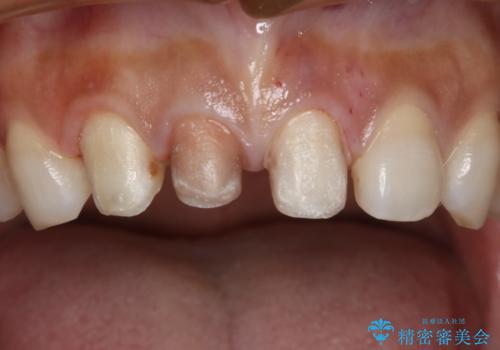

- 1週間ほど前に自転車で転倒して前歯をぶつけた後、歯の色が変わっていることが気になり受診された方です。診察の結果、失活及びエナメル質に多数の亀裂が認められたため、根管処置およびセラミッククラウンによる治療を行いました。元々右上2番目の歯の形が気になっていたとの事で、左右対称の形に近づけるように補綴しました。

左上1番目の歯は失活していませんでしたが、歯の表面に多数の亀裂が認められました。患者様のご希望により、前歯3本をまとめて補綴処置することとなりました。土台となる歯質の色が異なる状態でしたが、熟練した技工士さんの技術により3本とも同じ色味になるように仕上げていただきました。色味、形態ともに自然な被せ物に大変喜んでいただけました。